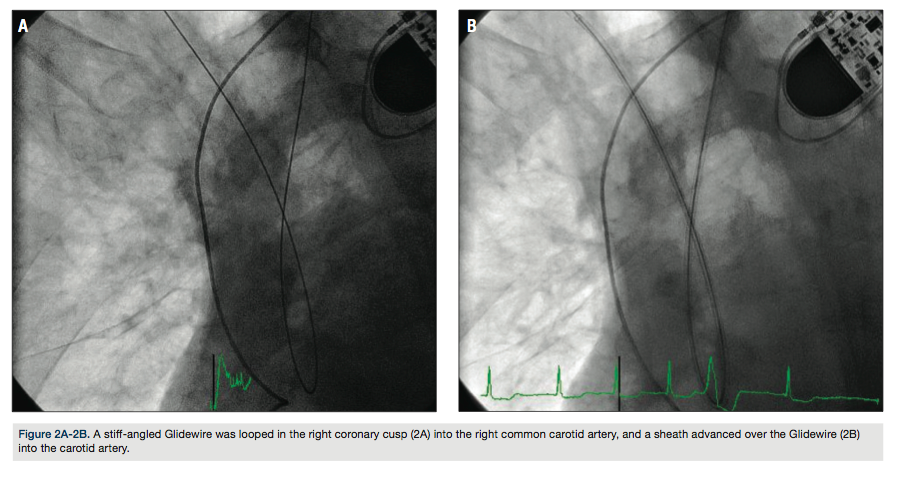

arch aortogram revealed a Type I aortic arch with no significant atheroma (Figure 1). A Simmons 2 catheter (AngioDynamics) was used to selectively engage the right common carotid artery by looping the catheter in the right coronary cusp. A stiff-angled Glidewire (Terumo) was then used as an anchor in the right external carotid artery (Figure 2A) and a Pinnacle Destination sheath (Terumo) advanced into the right common carotid artery (Figure 2B). Selective angiogram confirmed an 80% stenosis of the right internal carotid artery (Figure 3). An Emboshield distal embolic protection device (Abbott Vascular) was deployed in a straight segment in the distal right internal carotid artery. After pre-dilation with a Viatrac 4.0 x 20 mm

The right radial artery is the most common access utilized3, but the left radial technique has also been well established.5 For cases with poor guide support, the catheter looping and retrograde engagement technique (CLARET) has been described as an alternative strategy.6 This technique utilizes the right coronary cusp to loop the guide wire to engage the carotid artery, providing inferior support for the guide and sheath.